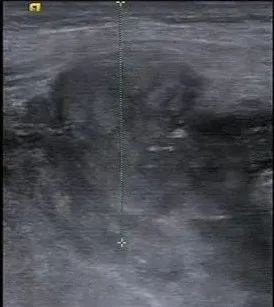

术中B超对肿物进行定位及测量